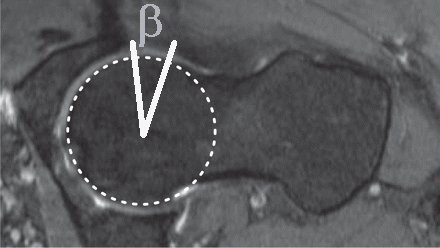

The range of movement before impingement is estimated from sectional images of the hip. A number of parameters have been measured, some completely different measurements have given the same Greek letter! Even reduced to two dimensions there are several parameters to consider:

Notes Clin Orthop Relat Res. 2012 Dec;470(12):3355-60. doi: 10.1007/s11999-012-2477-2. The acetabular wall index for assessing anteroposterior femoral head coverage in symptomatic patients. Siebenrock KA, Kistler L, Schwab JM, Büchler L, Tannast M Loss of rotation due to femoral neck thickening is quantified as the a angle (internal rotation) [ Do normal radiographs exclude asphericity of the femoral head-neck junction? Dudda M, Albers C, Mamisch TC, Werlen S, and Beck M. Clin Orthop Relat R, 2009, 467 (3):651–659. ] and ß angle (external rotation) [ Three-dimensional computed tomography of the hip in the assessment of femoroacetabular impingement. Beaulé PE, Zaragoza E, Motamedi K, Copelan N, and Dorey FJ. J Orthop Res, 2005, 23(6):1286–1292. ]. Available rotation after to acetabular pincer lesions is quantified as over coverage using the lateral centre edge angle, anterior centre edge angle. The combined loss of rotation due to femoral neck thickening and acetabular rim extension/reorientation is